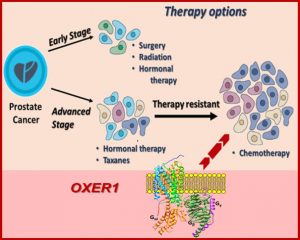

Τίτλος Ερευνητικού Έργου: Ανάλυση της δράσης και της φαρμακολογικής ειδικότητας του νέου λιπιδικού/στεροειδικού υποδοχέα OXER1 στη φλεγμονή και τον καρκίνο

Επιστημονική Υπεύθυνη: Καμπά Μαρία Ελένη (Μαριλένα)